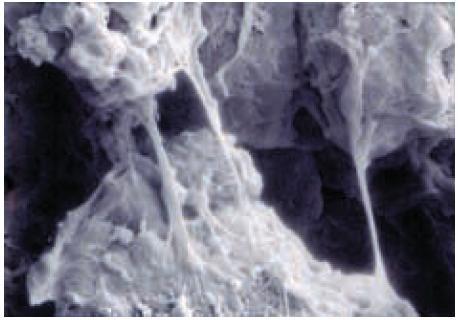

濕式造粒之應用

可使用快速高剪力混合造粒機(Super mixer),粉末加水約10%;

造粒顆粒大小,可以加水量及加水速率適度調節;

除作為親水間質控釋及膨脹劑外,亦作為顆粒與藥片結合劑;

快速釋出水分,可在15分鐘內浮床乾燥顆粒至含水率低於1%;

顆粒內膠體橋接(Bridging),見SEM圖,即使低於1%水分之顆粒,接續浮床混合45分鐘,亦無碎化現象